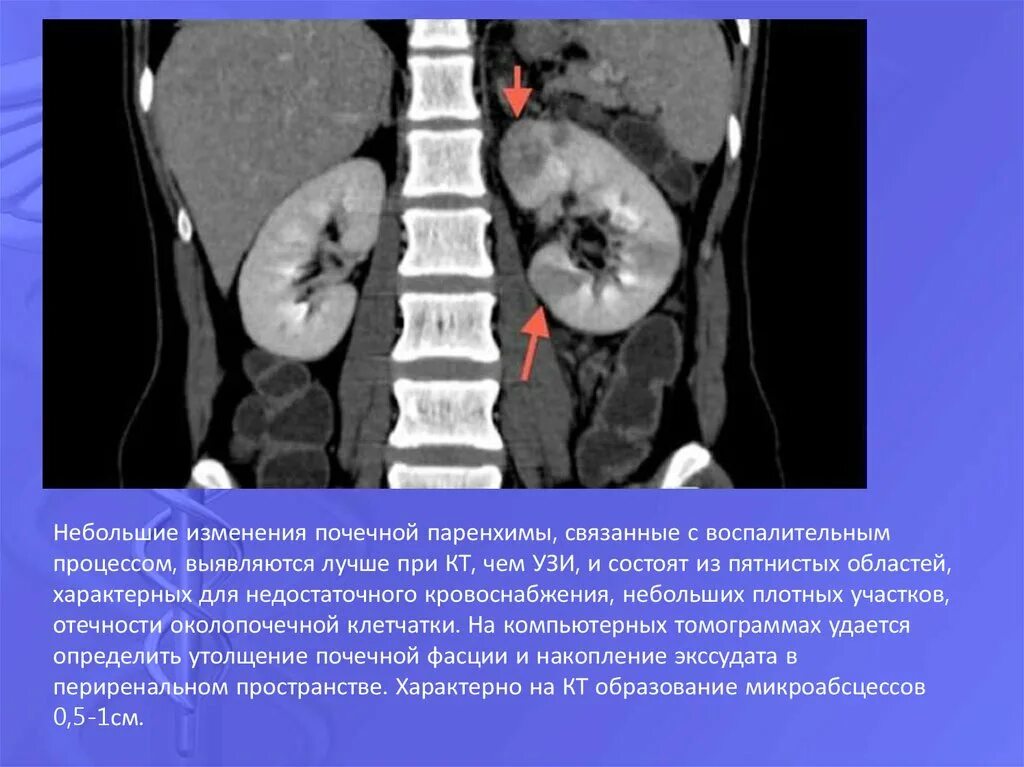

Пиелонефрит кт